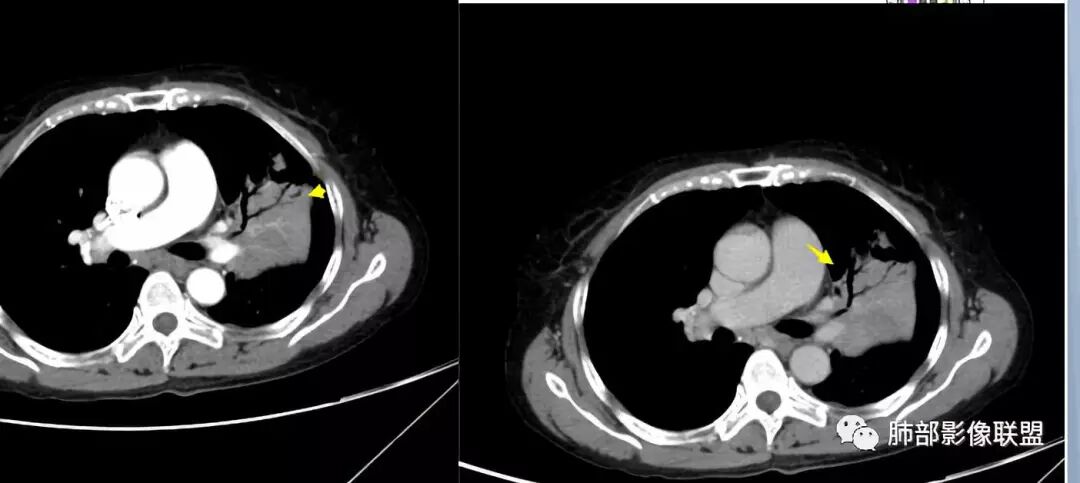

左上胸缩小,但是左上叶部分实变,边缘膨隆,内部有含气支气管,粘液栓,近端支气管堵塞

前端支气管通畅,部分稍扩张,走形自然

实变区支气管内粘液栓明显

上叶支气管堵塞处稍萎缩、凹陷,附近壁增厚,内可见小点状钙化

树芽征、小叶间隔增厚,淋巴结, 内部血管走形自然

分析:支气管粘液栓、支气管堵塞处萎缩、钙化,支气管通畅处部分扩张,树芽征——提示结核。

病灶膨隆明显,支气管堵塞,附近壁增厚,是否需要警惕恶性?

看这些钙化

前壁不厚,附近钙化灶太多,所以觉得结核一定要考虑,加上树芽征,就更支持。

支气管因为软骨,密度偏高,从这连续性看,支气管这一段的壁不厚,只是周围有病灶。

支气管壁软骨存在且连续,没有被破坏掉,支气管壁局部通畅,提示支气管壁没破坏,那么近端支气管癌肿不考虑。远端有树丫征,病灶周围很多钙化,所以结核一定有。